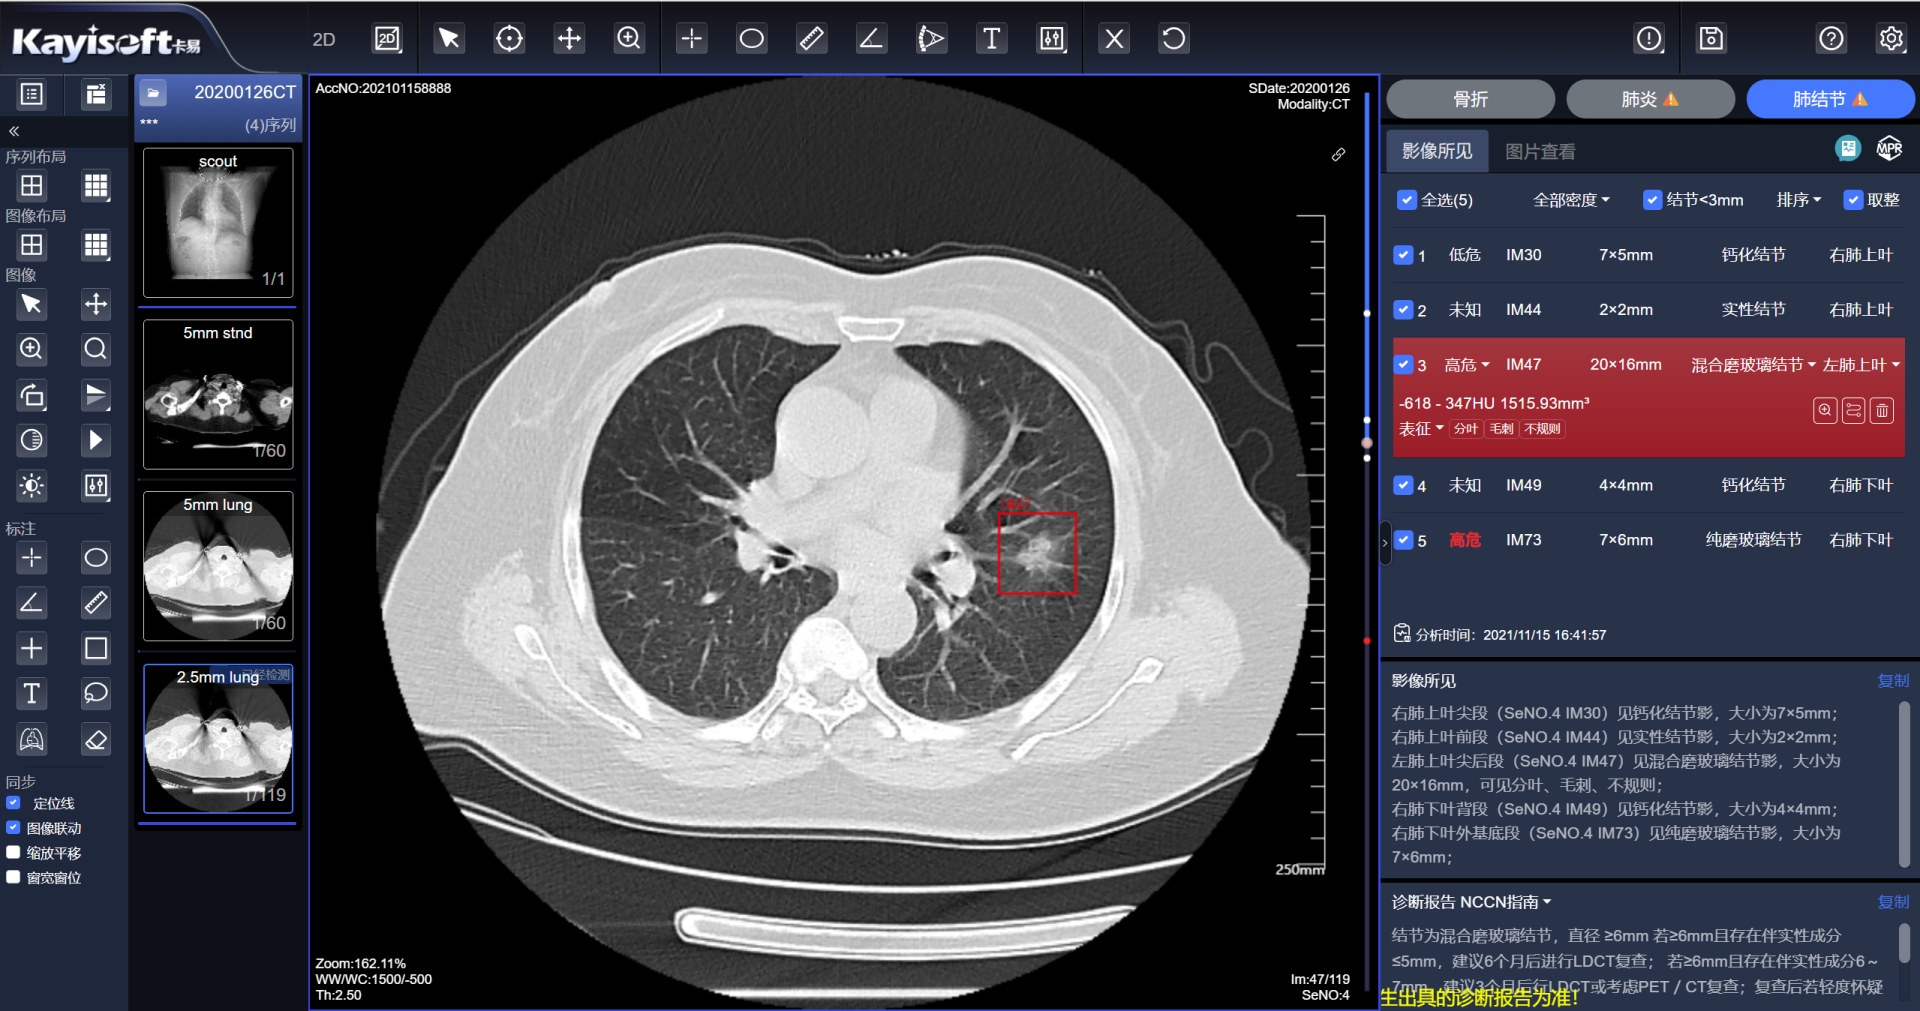

¡®¿µ½¡ÔƼ졯ƽ̨µÄÁÁµãÔÚÓÚÆäǿʢµÄAIÖÇÄÜÕï¶Ï¹¦Ð§¡£¡£¡£¡£¡£¡£¡£¸Ãƽ̨Äܹ»×Ô¶¯Ê¶±ðÓ°Ïñ£¬£¬£¬£¬£¬Ìṩ²¡ÔîÖÇÄÜÕï¶ÏÆÊÎö£¬£¬£¬£¬£¬²¢ÌìÉúͼÎĽṹ»¯±¨¸æ¡£¡£¡£¡£¡£¡£¡£Ïà½ÏÓڹŰåµÄÈ˹¤Á÷³Ì£¬£¬£¬£¬£¬Õâһϵͳ²»µ«ÄܽÚÔ¼´ó×Úʱ¼ä£¬£¬£¬£¬£¬Ìá¸ßЧÂÊ£¬£¬£¬£¬£¬»¹ÄÜÔÚÒ»¶¨Ë®Æ½ÉϱÜÃ⩼ìºÍÎóÕïµÄ±¬·¢¡£¡£¡£¡£¡£¡£¡£ÓÉ´Ë£¬£¬£¬£¬£¬Ò½ÁÆ×ÊÔ´Äܹ»ÊµÏÖ¼¯Öй²ÏíºÍ¸ßЧÉèÖ㬣¬£¬£¬£¬Èû¼ÕßµÃÒÔÏíÊܼÒÃſڵġ°AI+¡±¿µ½¡ÊØ»¤¡£¡£¡£¡£¡£¡£¡£

»ùÓÚÇøÓòÓ°ÏñÔÆµÄCT·Î½á½ÚAIÆÊÎö

ÕâÒ»Ó¦ÓÃͨ¹ýÓ°ÏñÊý¾ÝÔÆ»¯ÖÎÀíÊý¾ÝͳһÊÕÂÞ£¬£¬£¬£¬£¬ÊµÏÖÒÔÊý¾ÝΪ»ù´¡£¬£¬£¬£¬£¬ÍŽá AI ÆÊÎöЧÀÍ£¬£¬£¬£¬£¬ÊµÏַνá½ÚÖÇÄܱê×¢£¬£¬£¬£¬£¬½µµÍ©Õï¡¢ÎóÕïµÄ¸ÅÂÊ£¬£¬£¬£¬£¬½«ÕïÆ¬Ê±¼ä´Ó¹Å°åµÄ5·ÖÖÓ£¬£¬£¬£¬£¬Ëõ¶Ìµ½ÁË2-3·ÖÖÓ¡£¡£¡£¡£¡£¡£¡£